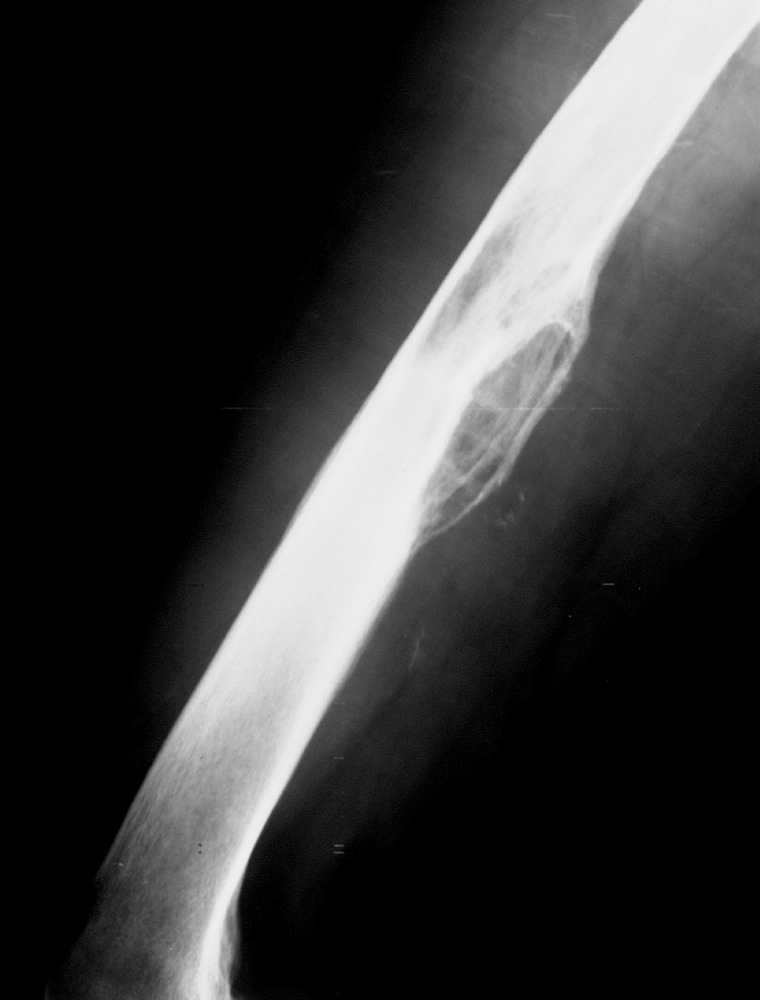

Skeletal Manifestations of Hydatid Disease in Serbia: Demographic Distribution, Site Involvement, Radiological Findings, and Complications

The Korean Journal of Parasitology 2013;51(4):453-459.